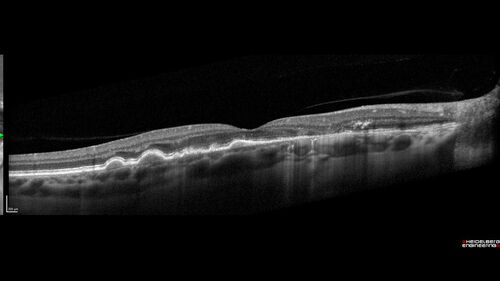

Dry AMD - Pigment - AREDS risk score of 4

65 year old woman with 20/32 vision. A little blurred. Pigment and large drusen in each eye. AREDS risk score of four.